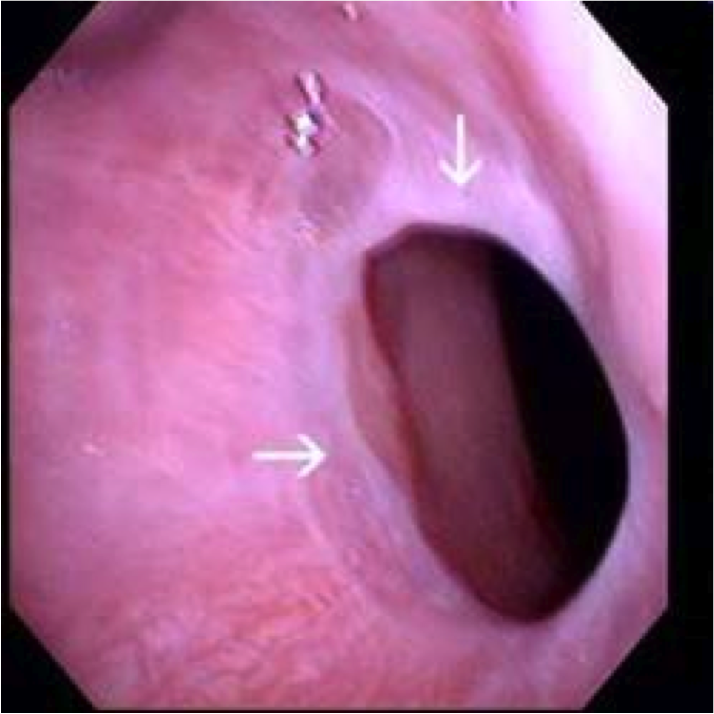

Esophageal diverticula

Outpouchings of the esophageal wall

- True = all layers, including muscle

- False = mucosa & submucosa only

- Zenker’s diverticulum = false, cervical esophagus, elderly (motor dysfx)

- Epiphrenic diverticulum = true, any age, just above diaphragm

Reflect underlying motor dysfunction

image=Zenker’s diverticulum